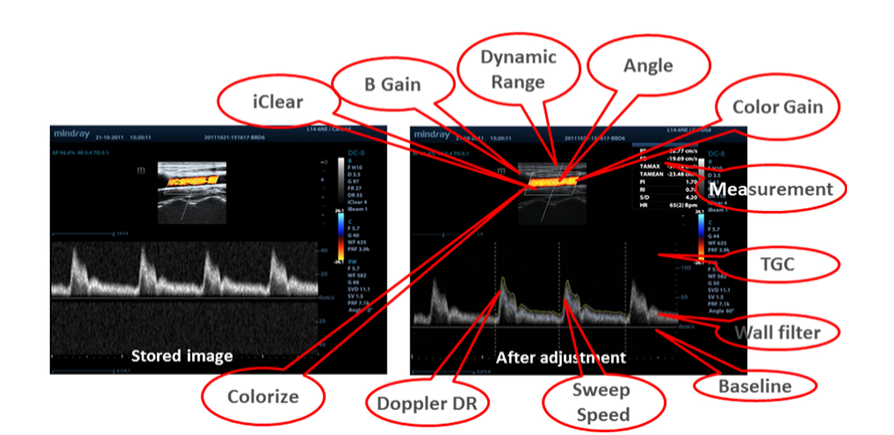

Data Mentah

Memungkinkan fleksibilitas optimum untuk pasca-pemrosesan gambar yang tersimpan, termasuk penyesuaian parameter, penambahan komentar dan pengukuran, sehingga memberikan produktivitas maksimum selama pemindaian.